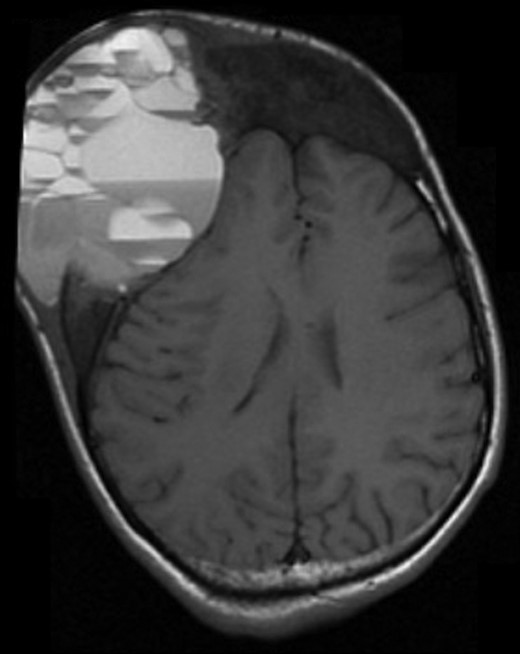

A computed tomography (CT) scan of the head 1-month after initial presentation revealed an aggressively appearing 5 cm × 5 cm soft tissue mass that was lytic and expansile involving the right frontal bone (Fig. 1). The lesion also involved the occipital bone with extension into the central skull base, nasal cavity and right nasal bone. Given the evidence of bone expansion and ground-glass appearance involving the calvarium, diagnosis was determined to be FD. Two weeks later, MRI studies revealed an aggressively enhancing 11 cm × 8 cm soft tissue mass with loculated fluid levels in the right frontal bone (Fig. 2). Extensive destruction of the outer table of the skull was noted with severe thinning of the skull inner table. Findings were thought to be consistent with ABC formation. Extensive bony involvement was noted primarily in the anterior and central skull base, but also in the occipital calvarium. Extension to the right zygoma and orbital walls with narrowing of the bony orbit was also visualized.